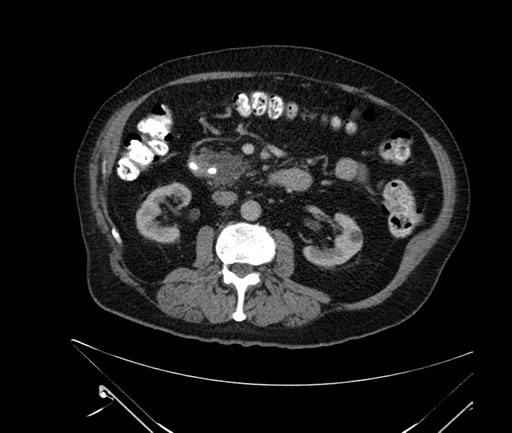

Whipple (pancreaticoduodenectomy) [case 7]

Imaging Analysis

Look through the patient's CT scan to identify any areas of concern for the necessary procedure.

Axial - 3 months prior